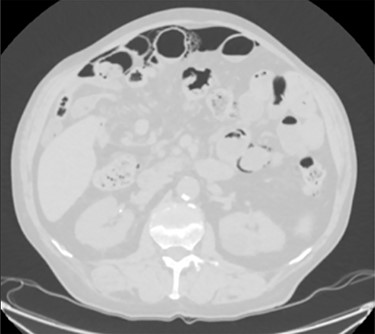

Unfortunately, once he returned home his temperature started to rise up to 38°C and he was readmitted to the hospital. A new contrast-enhanced Chest/Abdomen CT showed a bilateral pneumonia and a massive amount of intraperitoneal free gas, mainly in the abdominal upper quadrants (Fig. 2). No fat stranding, nondilated bowel, no vascular abnormalities and no free fluid were detected. Although the CT showed an evident worsening, the patient still remained completely asymptomatic on physical examination. Accordingly, he started to be treated with meropenem for pneumonia (Escherichia coli was isolated into the sputum) and he finally agreed to underwent diagnostic laparoscopy. Surprisingly, that was definitely not a case of pneumoperitoneum but an idiopathic PCI as we found multiple intramural air content cyst, about 2–3 cm in diameter, all around the small bowel loops and mesentery (Fig. 3). No intra-abdominal maneuvers were made. The patient had an unremarkable recovery (Clavien–Dindo classification grade was 1) [3] and he was discharged home on postoperative Day 15 in well condition, once he had recovered from pneumonia.

A moderate amount of intraperitoneal gas is present anteriorly to the small bowel.